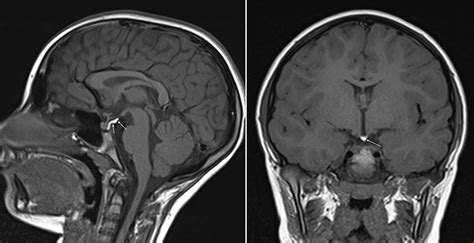

When patients present with symptoms related to hormonal dysregulation, a healthcare provider may order imaging to investigate the pituitary gland. This gland sits within a bony structure called the sella turcica. Because this area is quite intimate, standard brain scans may not always offer the resolution required to see micro-adenomas—very small tumors that can significantly affect hormone production. A dedicated pituitary gland MRI focuses specifically on this region, ensuring that even minute structural changes are identified.

Once the images are acquired, they are sent to a radiologist—a doctor who specializes in medical imaging. The radiologist carefully reviews the scans for any signs of enlargement, masses, or structural abnormalities within the pituitary gland or the surrounding tissues, such as the optic chiasm. The findings are documented in a comprehensive report, which is then sent to the physician who ordered the scan. Your doctor will then correlate these findings with your blood work and clinical symptoms to determine the next steps in your care.